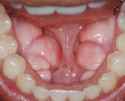

When you stimulate the jaw the teeth must also be conditioned and with this comes what are called Toris.

Toris are found on both the outside of the gums and the inside and can cause very serious complications for breathing, swallowing food/water as they crowd your mouth.

They require surgery to be removed.

However once again, it is legitimate it will stimulate your jaw.